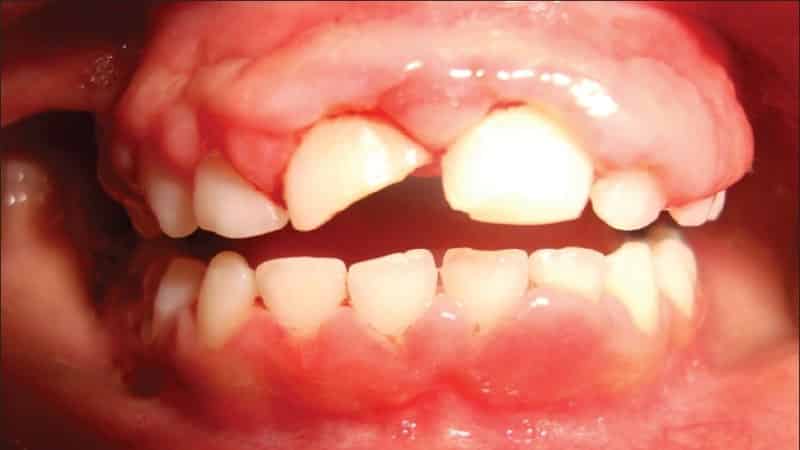

Гипертрофическая форма чаще всего проявляется в период полового созревания. Также она может быть связана с нехваткой витамина С в организме. Это заболевание затрагивает участки челюстей, где зубы плотно соприкасаются друг с другом. Воспаление может охватывать одну или несколько десен, иногда затрагивая обширные участки с несколькими зубами. Воспаленные сосочки на деснах могут покрывать зубы.